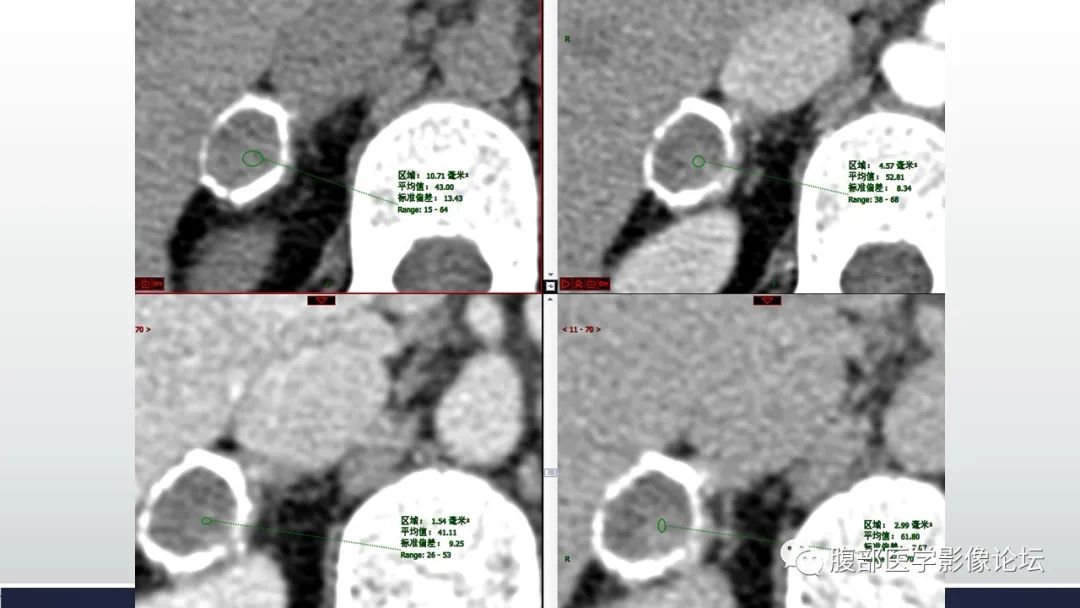

徐钢:环形钙化,里面有轻度强化,静脉期退出,延迟又有强化,不知是不是测量的问题,但是延迟确实看到有强化,我考虑良性病变,倾向感染类,结核?至于临床症状有否,要看确切的临床资料

定量:环形钙化,中心密度减低为主,见少许密度稍高区,增强扫描未见强化;中年女性,平素健康。

医风听雨:右侧肾上腺蛋壳样钙化病灶,内部密度不均,(40到60多),这种表现很少见,分析只能一一排除,肿瘤(包括原发和转移),炎症,囊肿。肿瘤的话考虑良性肿瘤,炎症没有特别适合的病变,囊肿可以边缘钙化,但是这个病灶钙化比较厚,不符合。总结还是考虑良性肿瘤。 医学百科网 | YxBaike.Com